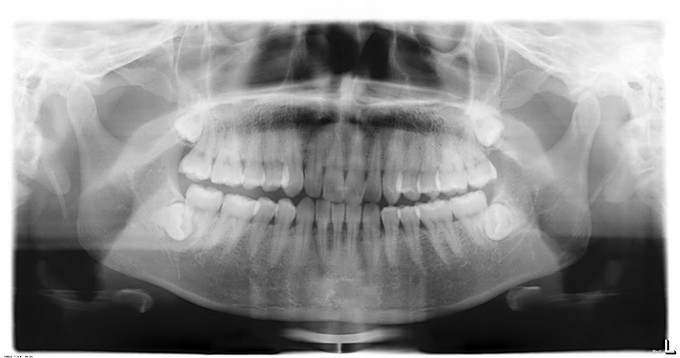

发现上下颌阻生牙1周,者于1周前无明显诱因出现右下后牙疼痛,冠周冲洗后疼痛症状缓解,外院全景片示:18、28、38、48阻生齿。今为进一步治疗来我院就诊,门诊以"18、28、38、48阻生齿"收入院。

口内检查:18、28、38、48未萌出

诊断:18、28、38、48阻生齿,全麻下行“18、28、38、48阻生齿拔除术+牙槽骨修整术+邻近瓣转移修复术”手术。手术经过顺利术后予预防感染、消肿、止血等治疗